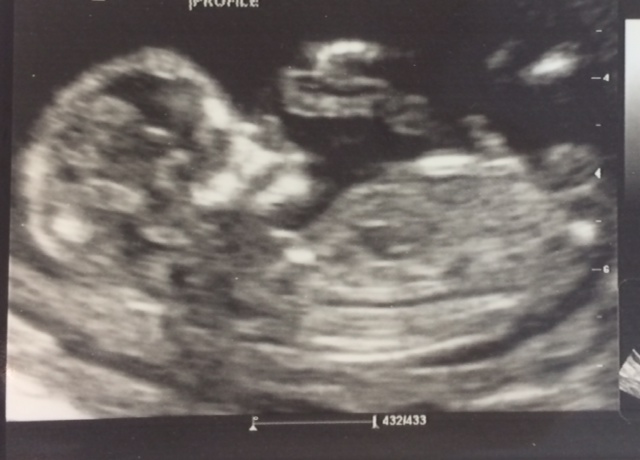

I think that bit sticking up is the cord and I don't see a nub sorry. Hope you get your DG :)

can't tell, did you get a diff. picture?